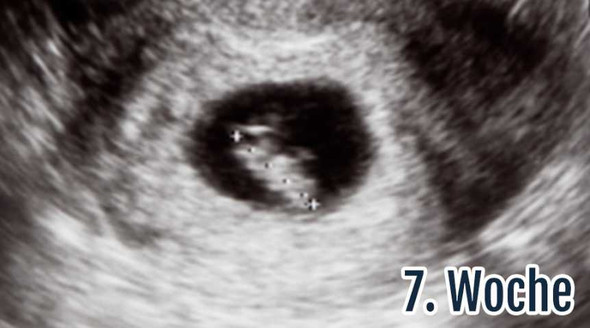

SSW dar, sondern erscheint leicht queroval Hier wurde zwar nicht gemessen, aber in Relation zur Gebärmuttergröße kann man den Durchmesser der Fruchthöhle auf ca einen Zentimeter schätzen Auch hier ist der Embryo noch nicht erkennbar Ultraschallbild 53 SSW Ein weiteres Ultraschallbild vom 3 der 6 Schwangerschaftswoche (53). 6 4 ssw ultraschall nur fruchthöhle Anzeichen, Symptome & Ultraschall in der 6 SSW In der 6 Schwangerschaftswoche kann im Ultraschall der Herzschlag des Babys bereits sichtbar werden, auf jeden Fall ist die Fruchthöhle als schwarzes Oval und der bohnenförmige Embryo erkennbar 6Schwangerschaftswoche (6. Ultraschall in der 61 SSW nur Fruchthöhle und Dottersack sichtbar Tamara92 1 0812 Uhr in Schwangerschaft Hallo zusammen Ich bin 28 Jahre und bin nach einer 2 jährigen Kinderwunschbehandlung während der ersten ICSI schwanger geworden🥰.

Heute war ich nun zum ersten Ultraschall (vaginal) und es war leider nur eine leere Fruchthöhle, aber kein Dottersack und auch kein Embryo zu sehen Der HCGWert war bei Praxisschluss leider noch nicht fertig (musste laut Schwester noch "verdünnt werden") läge aber angeblich bei über 5000 Den genauen Wert erfahre ich morgen früh. War am 247 beim Frauenarzt, da war ich laut Rechnung 55 ssw Man konnte nur eine leere fruchthöhle erkennen. 5 ssw ultraschall nur fruchthöhle Schwangerschaft 6 Woche (6 SSW) Ultraschallbilde Hier sieht man deutlich die schwarze Fruchthöhle, der Embryo lässt sich noch nicht erkennenMan sieht aber ebenfalls sehr deutlich, dass es sehr darauf ankommt, wie der Arzt bei der Untersuchung die Messpunkte setzt.

6 4 ssw ultraschall nur fruchthöhle Anzeichen, Symptome & Ultraschall in der 6 SSW In der 6 Schwangerschaftswoche kann im Ultraschall der Herzschlag des Babys bereits sichtbar werden, auf jeden Fall ist die Fruchthöhle als schwarzes Oval und der bohnenförmige Embryo erkennbar 6Schwangerschaftswoche (6. Fehldiagnose 8 ssw nur Fruchthöhle und Dottersack Hallo, ich möchte mich hir einmal auskotzen Ich habe gestern meine 4 Untersuchung gehabt Davon 1 x Blutabnahme, sonst nur Ultraschall Schnell schnell Untersuchungen und gestern dann die Diagnose 'missed abort' Überweisung in die Klinik weil nur Fruchthöhle und Dottersack zu sehen sind und ausgeschabt werden muss. In der Frühschwangerschaft können Frauenärzte nicht immer bei der ersten Ultraschalluntersuchung das Baby oder den Herzschlag im Ultraschall erkennen Es kommt öfters vor, dass um die 6SSW nur eine leere Fruchthöhle zu sehen ist In den meisten Fällen handelt es sich darum, dass das Baby etwas kleiner ist als bisher angenommen.